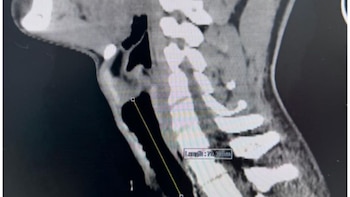

El joven presentaba una estenosis traqueal severa, una obstrucción casi total de la tráquea, consecuencia de una intubación prolongada y una traqueostomía practicadas dos años atrás, tras sobrevivir a una herida de bala. El tejido cicatricial generado por ese antecedente bloqueó el paso del aire y le impedía realizar actividades cotidianas.

La compleja cirugía estuvo a cargo de los especialistas en cabeza y cuello, doctor Risto Mendoza Cueva y Dr. Renato Mejía Rodríguez, quienes lideraron el procedimiento durante aproximadamente cuatro horas. El equipo extrajo un segmento dañado de unos cinco centímetros y posteriormente unió los extremos sanos de la tráquea para restablecer el flujo respiratorio.